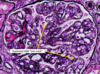

Renal Cell Carcinoma

Clear Cell RCC

Clear Cell RCC

Papillary RCC

Papillary RCC

Chromophobe RCC